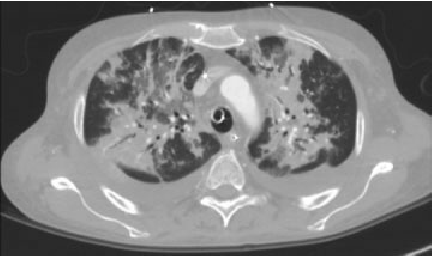

• Klinik, laborator və tomoqrafik üsullarla törəmənin təbiəti məlum olmursa rezektabelliyə görə qərar verilir (Şəkil 20). Rezektabel törəmələrdə kütlə əməliyyatla (torakoskopik və ya açıq) çıxarılır və histoloji müayinə edilir (həm diaqnostika, həm də müalicə məsələsi həll edilir). Qeyri-rezektabel törəmələrdə isə perkutan, bronxoskopik və ya torakoskopik yolla biopsiya edilir.

Şəkil 20. Divararalığında kütlə